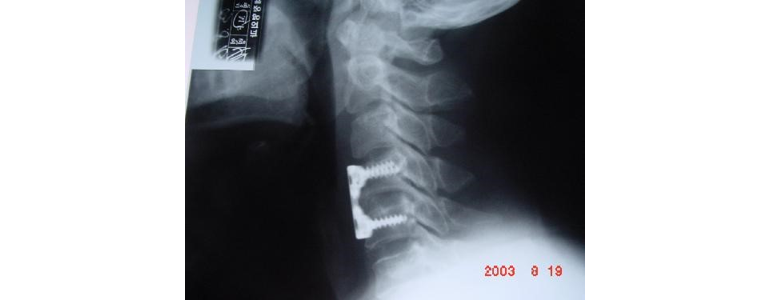

물리치료를 받기 전에는 본인의 증상에 대해 자세히 기록해 가는 것이 좋습니다. 또한, 치료를 받을 때 편안한 복장과 함께, 이전의 의료 기록이나 X-ray 사진을 준비하면 병원에서 정확한 진단을 내리는 데 도움이 될 수 있습니다. 준비물을 빠짐없이 챙겨 가면 치료를 더 효율적으로 받을 수 있습니다.